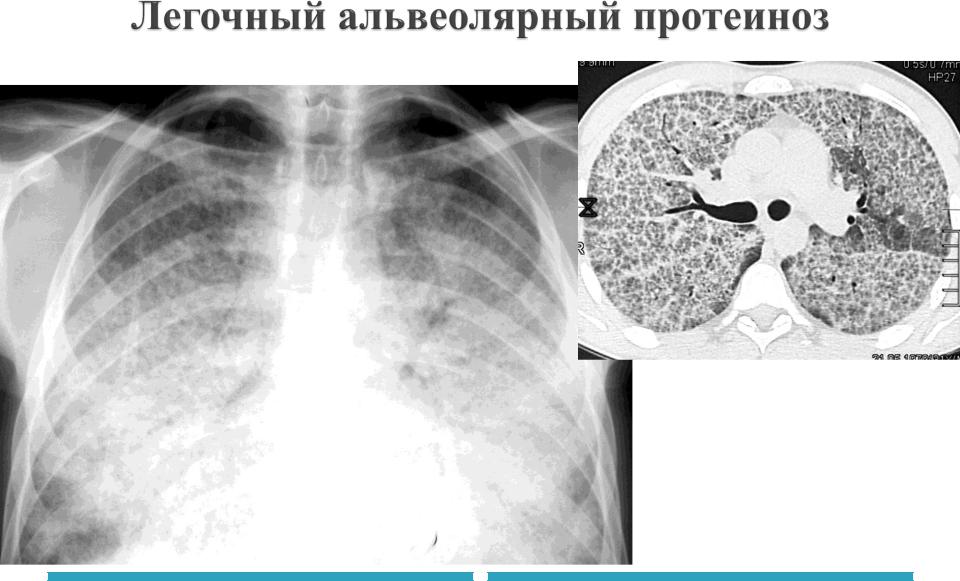

Скопление липопротеинов в альвеолах

Начало

бессимптомно

Диагностика – БАЛ, цитология

Лечение – БАЛ+ симптоматическое